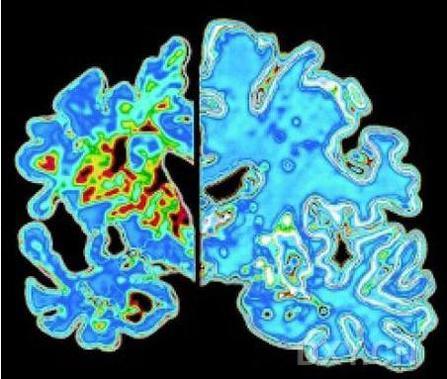

在对自然清除机制研究了近十二年后,Landreth的研究重点转向一组类似于吞噬分子的能帮助吞噬和移除淀粉样蛋白细胞受体。幸运的是,制药企业已经研制除了一种可以易化这个过程的药物:治疗癌症的蓓萨罗丁。当Landreth的研究生,Paige Cramer将这种药物注射入存在阿尔兹海默病症状的小鼠中时,这些小鼠脑内异常出现了快速逆转。在服用药物24小时内,小鼠的脑脊液中淀粉样蛋白减少了25%;在2周后,由淀粉样蛋白组成的粘性斑块降低了75%。

这并不意味着阿尔兹海默病患者可以让医生给他们服用蓓萨罗丁。阿尔兹海默病的小鼠模型并不是完美的。小鼠产生阿尔兹海默病的方式并不等同于人类。它们的脑内产生了淀粉样蛋白,积存的淀粉样蛋白形成了能损害神经功能和影响学习和记忆的斑块,这些和在阿尔兹海默病患者脑内的变化一致,但在小鼠中,情况并不会出现恶化,也不会导致神经纤维的破坏。人类丧失了脑细胞,死亡的神经网络碎片积聚破坏了功能。

但是这要求我们在疾病发生早期就能识别出阿尔兹海默病患者。这并不是一件容易的事。最近的研究提示淀粉样蛋白的产生和神经细胞的破坏早在出现记忆丧失或其他认知改变的数十年前就出现,定位这些疾病早期阶段需要更复杂的方法来追踪淀粉样蛋白或使用影像学技术提示大脑的改变。科学家们在这方面做了部分工作,如对阿尔兹海默病的诊断标准进行了最新修订,提出疾病的先兆如轻度认知障碍,反应了对疾病早期阶段的认识不断加深。但是诊断界限仍然模糊,研究者们仍然在辩论年龄相关的记忆损害和阿尔兹海默痴呆的早期记忆损害的区别。